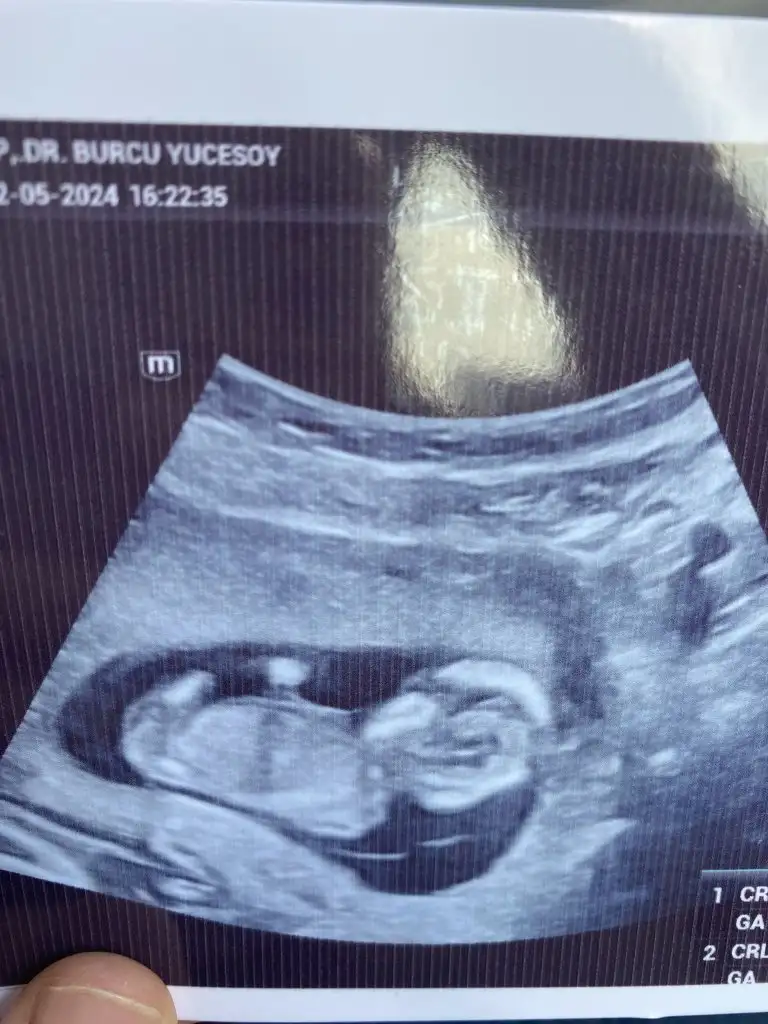

Merhaba erkek gibi benim ultrasonuda yorumlarmisiniz acaba

• IMG-20240308-WA0003.webp

IMG-20240308-WA0003.webp

12,2 KB · Görüntüleme: 60

Erkek gibi hayırlı olsun benim ultrasonda yorumlayacak birisi varımdır acaba